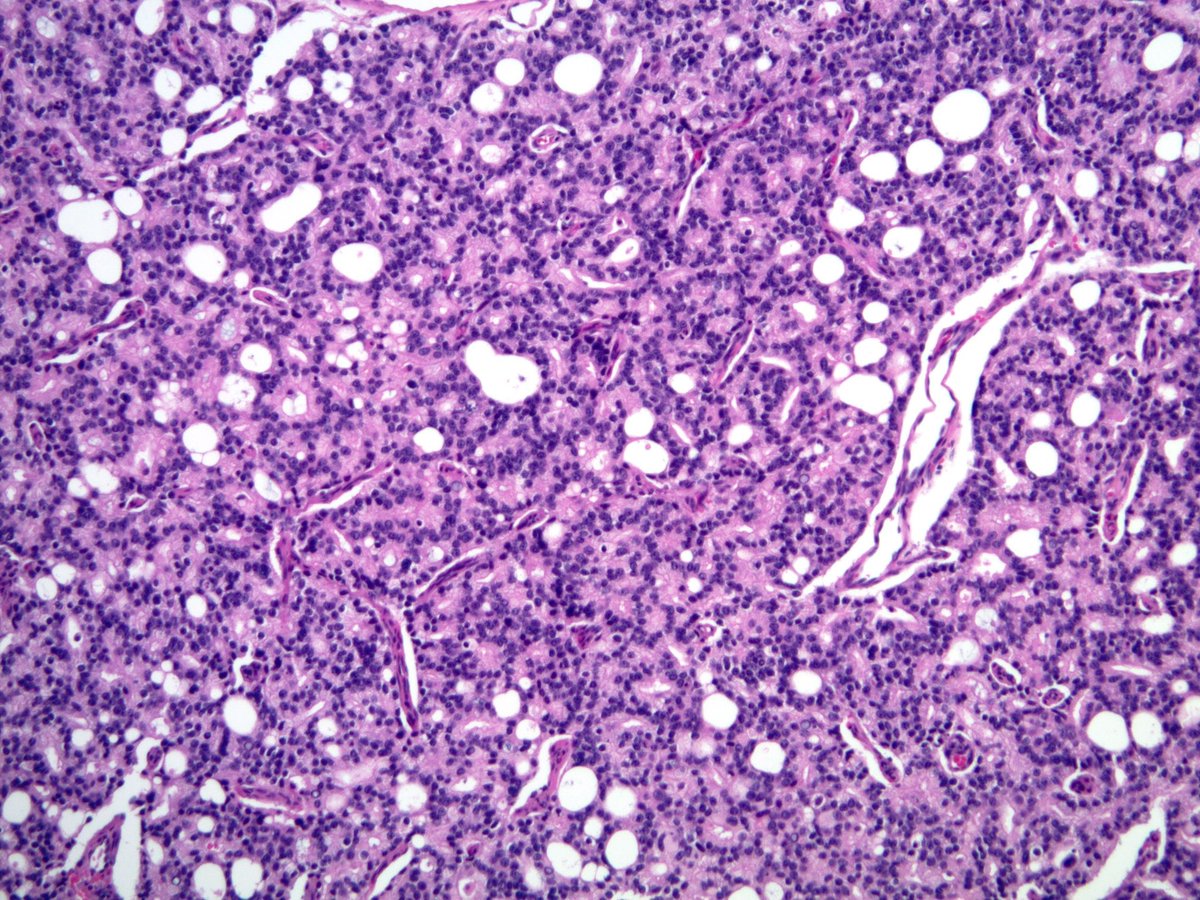

@smlungpathguy

Thoracic masses. Can you guess how many immunostains were done and why? #pathology #pulmpath